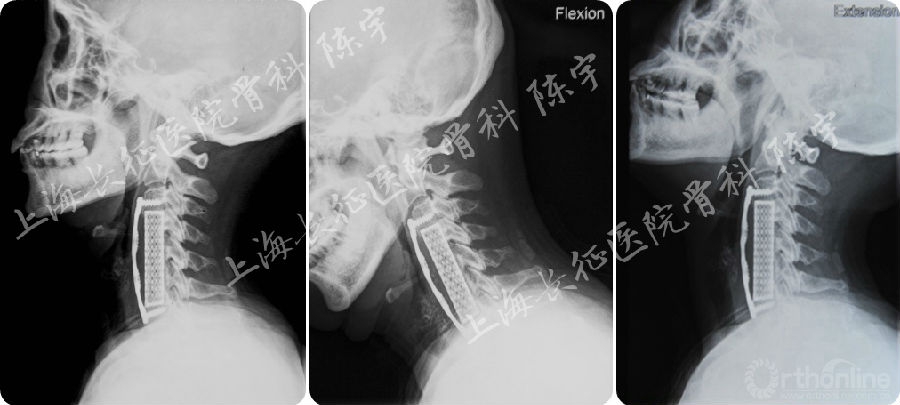

术前影像学检查(图1):

(1) X线:颈椎侧位及伸屈侧位片显示颈椎呈后凸畸形;

(2) MRI:颈4-6水平脊髓严重受压;

(3) CT: 颈4-6连续型后纵韧带骨化,在最严重水平椎管狭窄率达到90%以上,在横断面上表现为典型“双影征”,提示合并硬膜囊骨化。